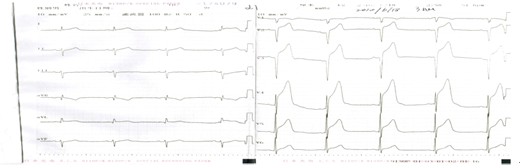

2010(96-98)女性,74岁,1周前因股骨颈骨折卧床行保守牵引治疗。8小时前在睡眠中突发心前区疼痛,持续伴阵发加重,出汗,口含硝酸甘油不缓解。既往有高血压、糖尿病史。入院查体:脉率62次/分,血压110/70mmHg,双肺(一),心脏不大,心律整,A2>P2,双侧脉搏对称。

心电图如下所示

96.对该患者最可能的诊断是( )

A、肺栓塞;

B、主动脉夹层;

C、不稳定性心绞痛;

D、急性心肌梗死

97.为明确诊断,最有价值的检查是( )

A、肌酸激酶同工酶(CK-MB);

B、D --二聚体(D-Dimer);

C、肌钙蛋白T(TnT) ;

D、脑钠肽(BNP)

98.下面关于该患者的急诊处理措施,错误的是

A、溶栓治疗;

B、抗凝治疗;

C、抗血小板治疗;

D、急诊介入治疗

考点:心电图阅读;急性心梗的诊断;溶栓禁忌症